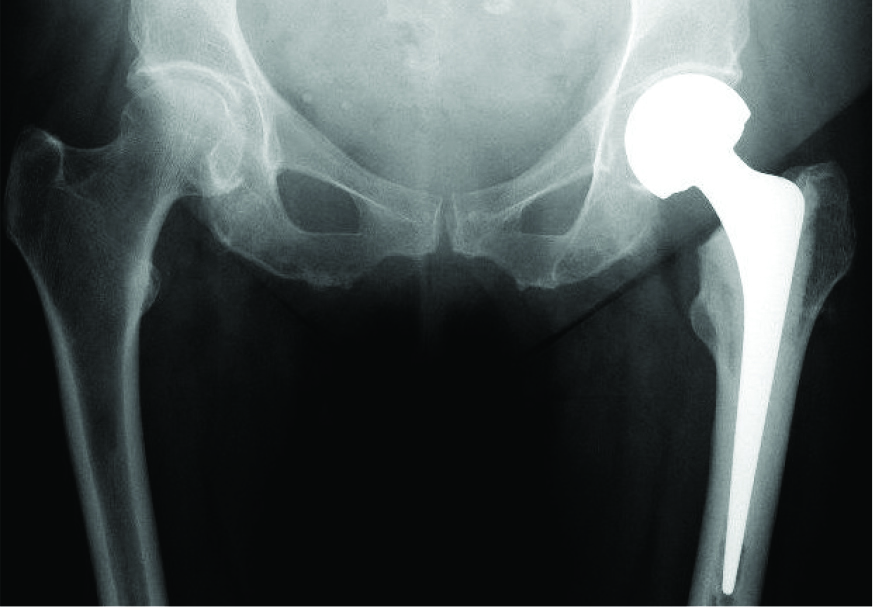

This is a total hip replacement

If the fracture is in the neck of the femur, the blood supply to the head of the femur will be compromised, and a partial or total hip replacement will be necessary.